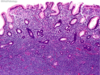

A patient has a gastric antral biopsy for abdominal pain, the slide of which is pictured. How does this organism survive in the acidic stomach?

A. Ammonia production

B. Hydroxide production

C. Bicarbonate production

D. Sulfate production

A. Ammonia production

H. pylori has a urase, which converts urea and water to CO2 and ammonia, which neutralizes gastric acid.